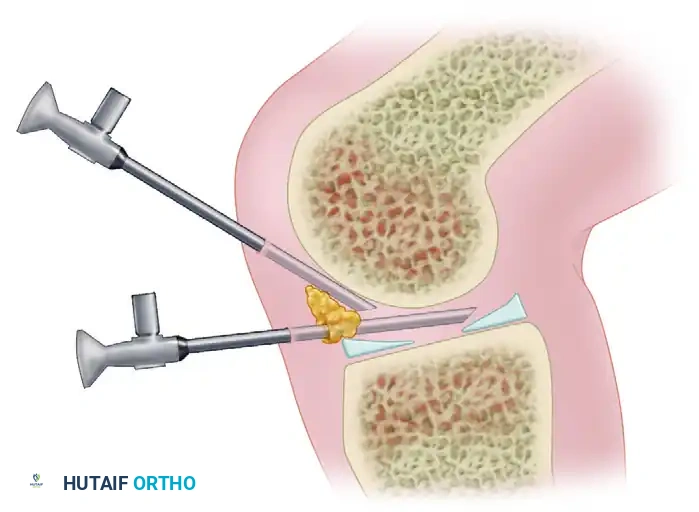

Once the portals are established, instruments are introduced using the principle of triangulation. The arthroscope and the working instrument (e.g., probe, punch, or shaver) converge at the target pathology, forming an apex.

Essential for repairing posterior horn meniscal tears, addressing posterior ramp lesions, and extracting loose bodies residing in the posteromedial recess.

* Prerequisites: The knee must be flexed to exactly 90 degrees, and the joint must be maximally distended. This causes the posteromedial capsule to balloon outward, displacing the saphenous nerve and vein posteriorly.

* Location: Approximately 1 cm superior to the posteromedial joint line and 1 cm posterior to the posteromedial margin of the medial femoral condyle.

* Technique: Transillumination with the arthroscope from the intercondylar notch can highlight the superficial venous structures, allowing the surgeon to make a safe skin incision.